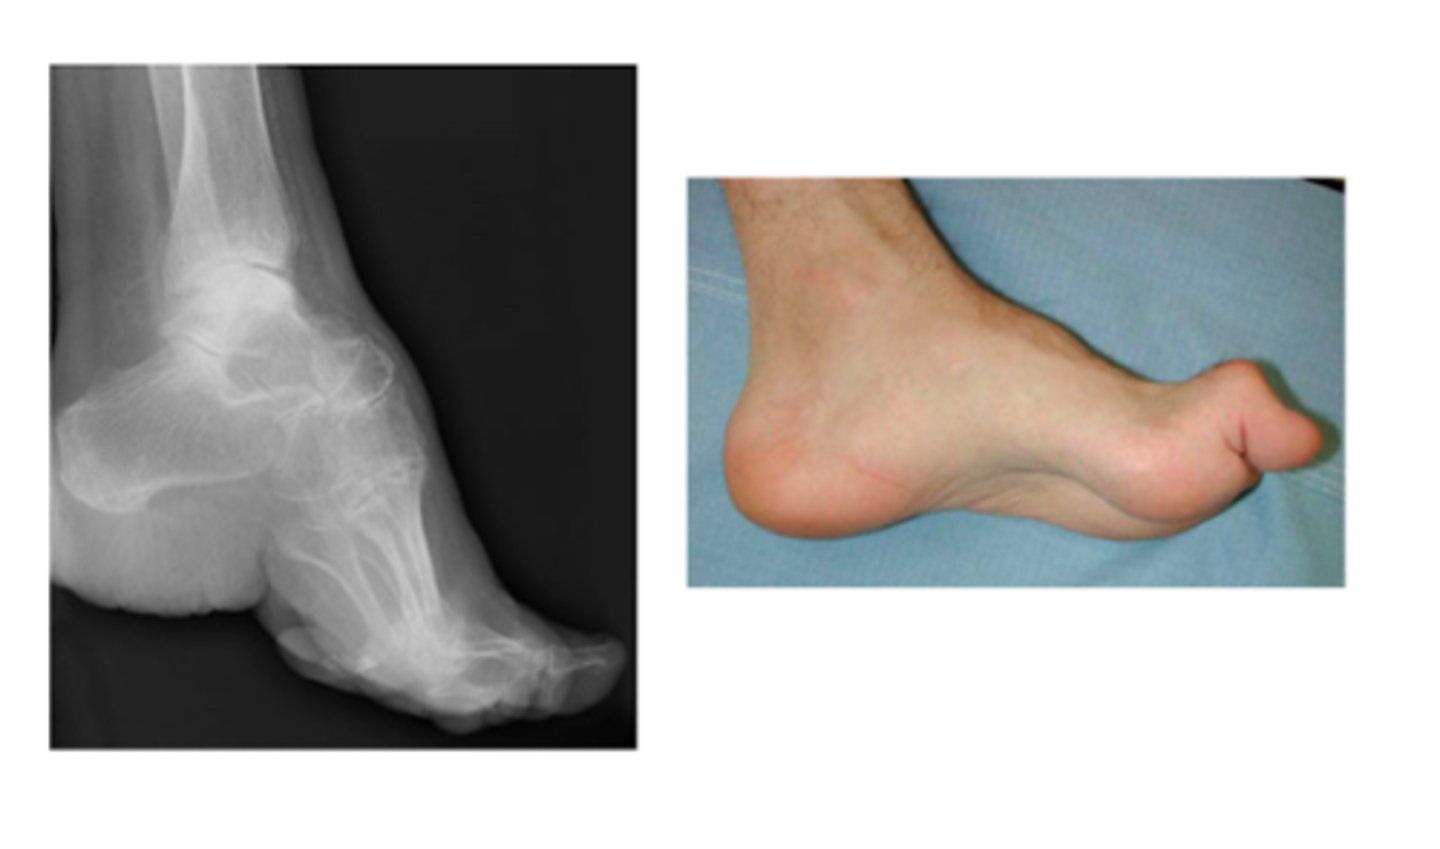

What is the difference between pes cavus and pes planus?

Pes cavus → elevated longitudinal arch

Pes planus → no longitudinal arch (flat feet)

What is the treatment for pes cavus?

surgery

What is the treatment for pes planus?

PT

Arch support

NSAIDs

If ADLs affected → ortho referral

What TWO findings on XR are suggestive for Charcot's foot?

Decline in calcaneal inclination with equinus (inability to dorsiflex)

Rocker-bottom deformity

**will initially not appear on XR